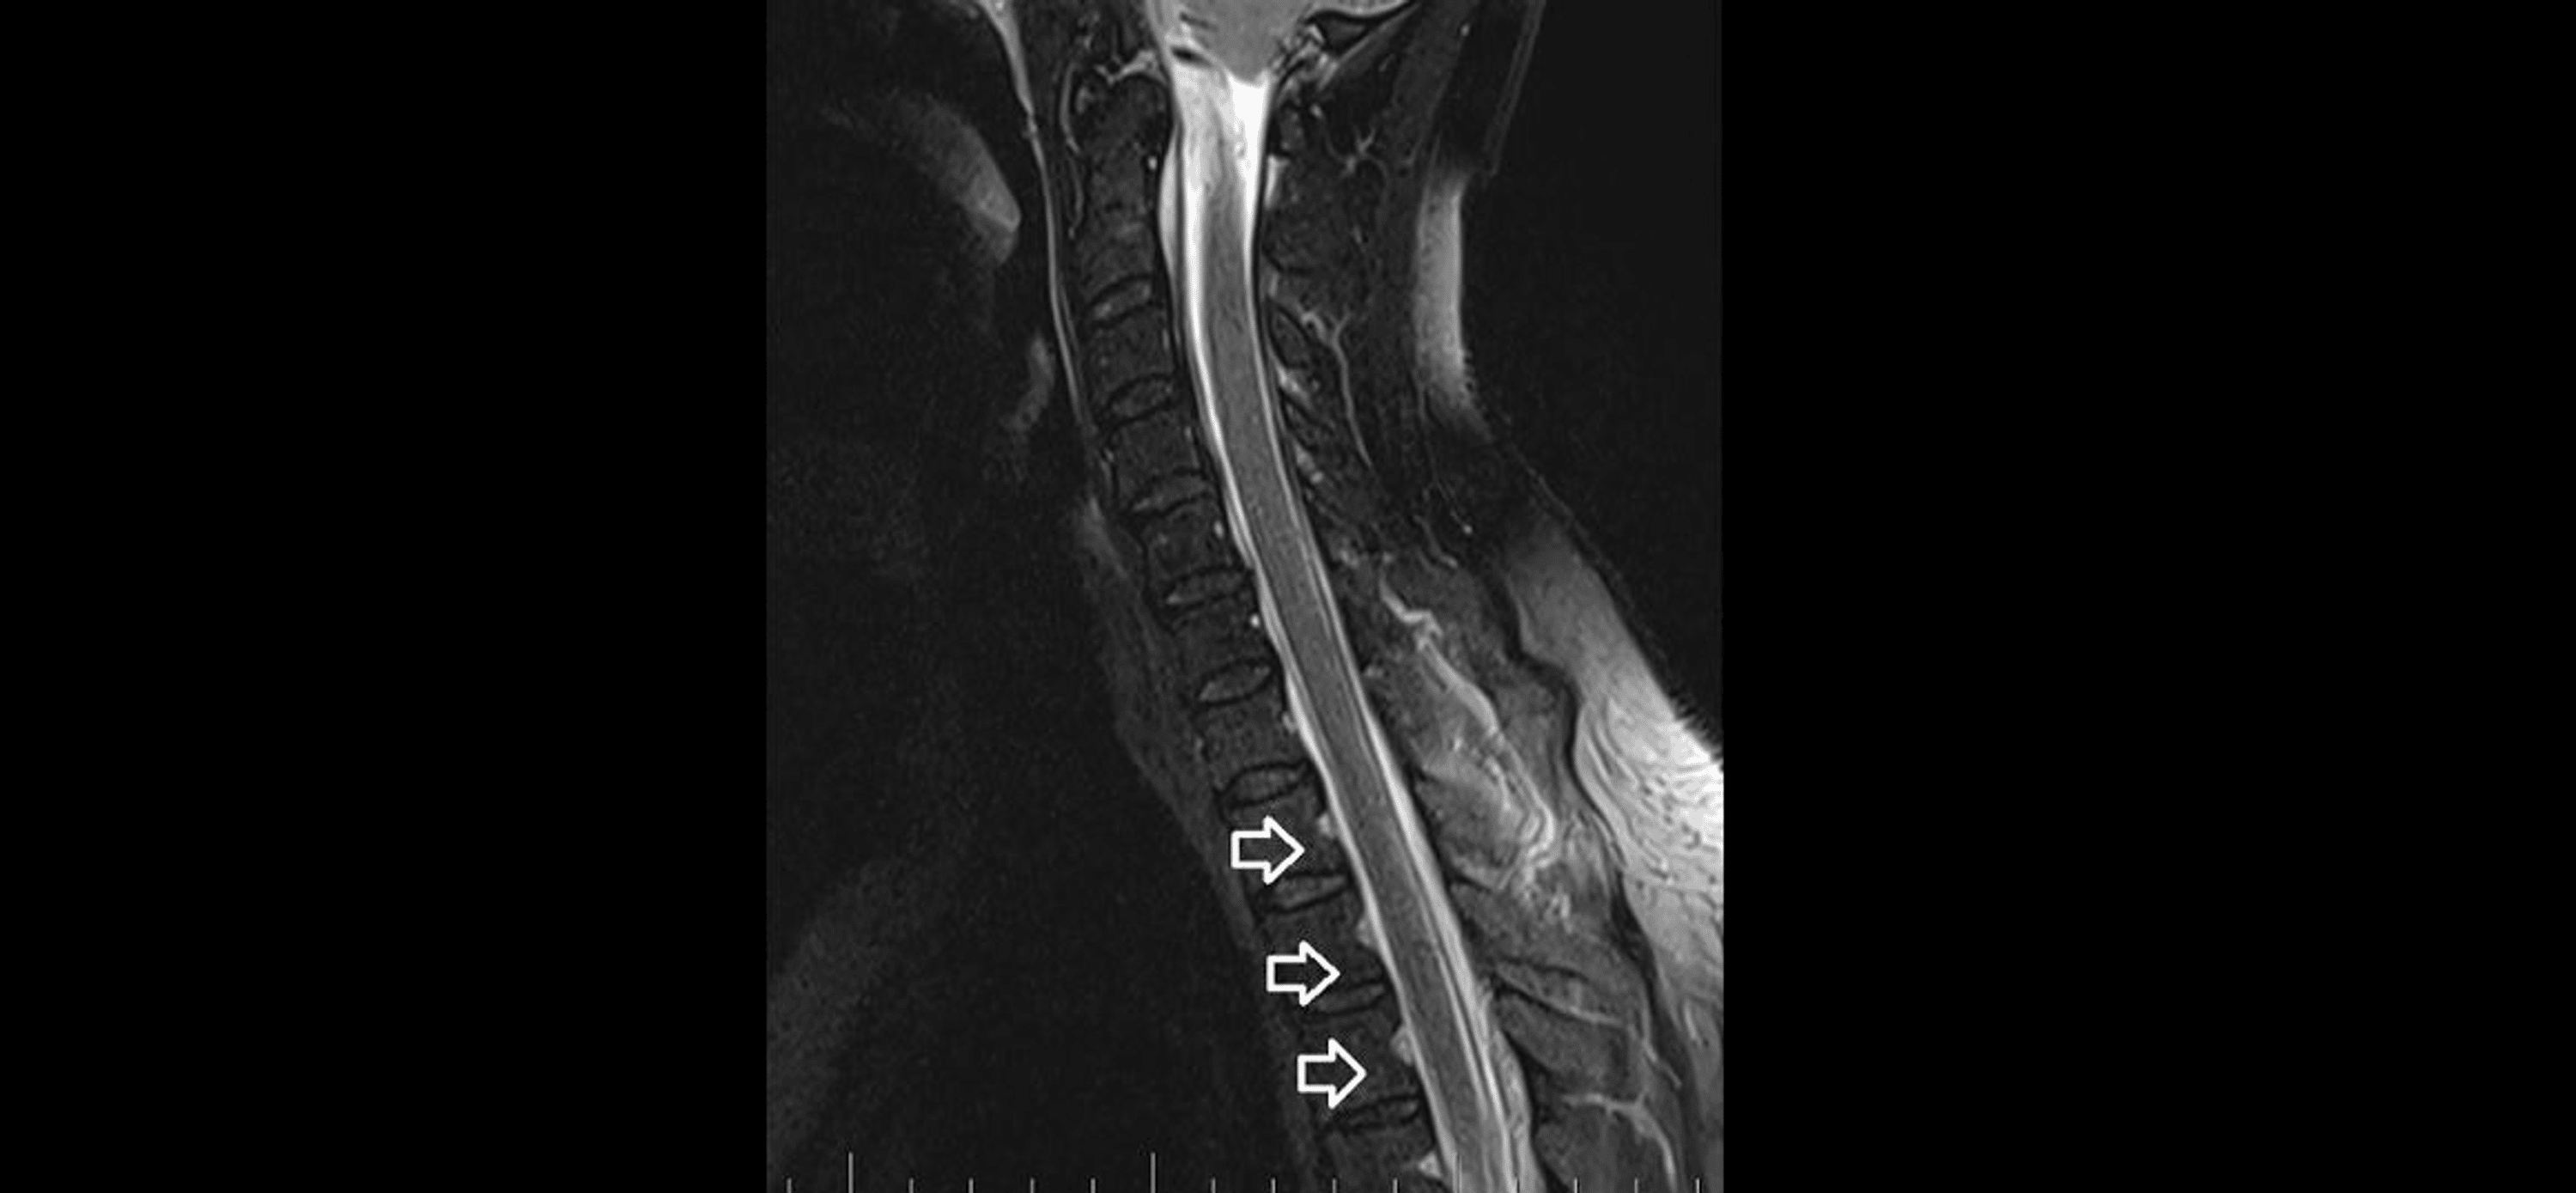

As part of the differential diagnosis, further imaging was performed. A brain MRI on February 1, 2023 (Figure 1) showed the following signs of SIH: subdural fluid collection up to 5.00 mm in the parietal area; diffuse, smooth dural thickening and pachymeningeal contrast enhancement; slightly homogeneous enlargement of the pituitary; cerebellar tonsillar descent into the foramen magnum; distension of the cerebral venous sinuses without thrombosis; and reduced fluid volume in the optic nerve sheath.

Precisely locating the site of the CSF leakage is fundamental to successful treatment [8]. Hence, on February 2, 2023, we performed a C spine MRI. At the level of C7/T1/T2, a T1 right foraminal CSF leak, as well as the spinal longitudinal extradural fluid collection (SLEC) caudal to the C5 level was detected (Figure 2). This finding confirmed the CSF leak outside the dural sac. It was an SLEC 1b type of CSF leak [4].